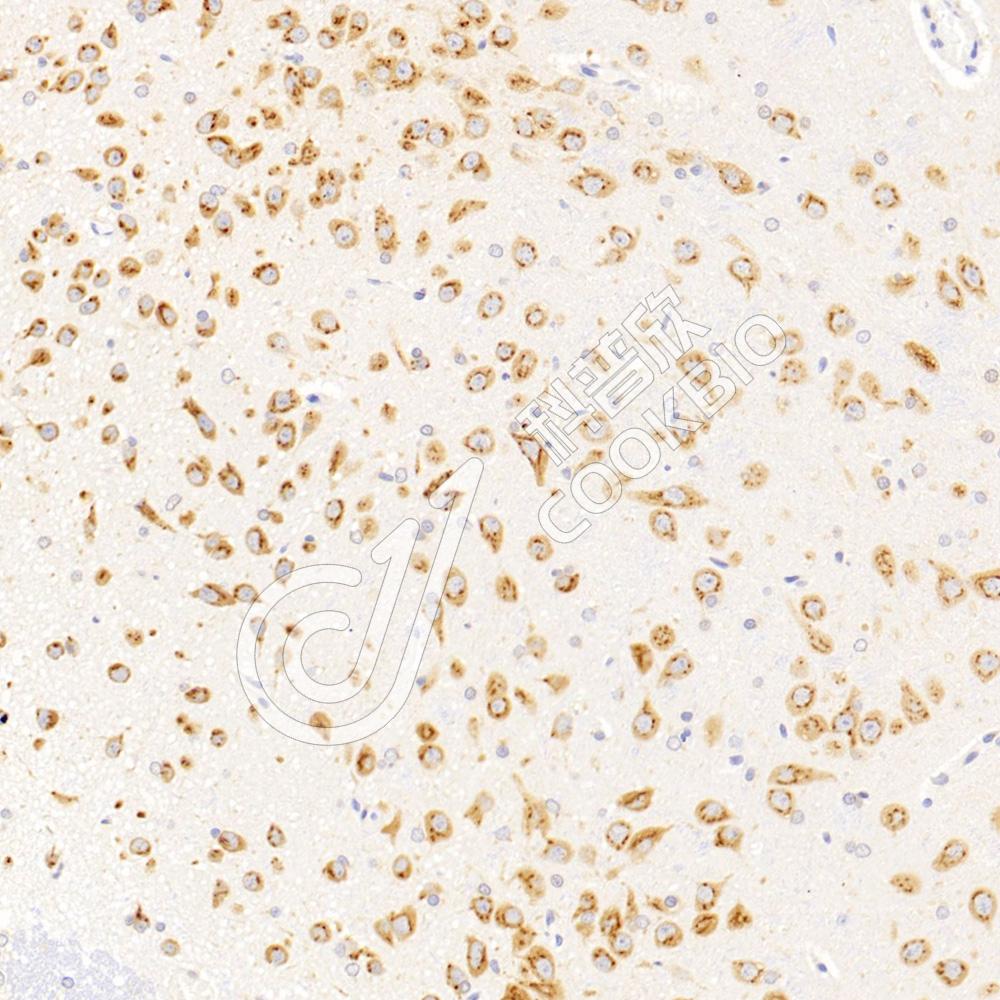

IHC检测VAMP4蛋白(货号 K1340236).

样品: 小鼠脑, 4%多聚甲醛 (货号KSG1101) 固定12-24小时.

抗原修复: 柠檬酸抗原修复液(干粉, pH 6.0) (KSG1201), 98℃, 20分钟.

—抗: 1: 2300稀释, 4℃ 孵育过夜.

二抗: S-vision免疫组化多聚二抗(山羊抗兔),即用型 (货号KB3906), 室温孵育20分钟.

样品: 大鼠脑, 4%多聚甲醛 (货号KSG1101) 固定12-24小时.